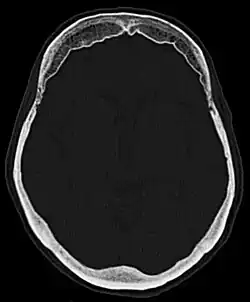

Die Hyperostosis frontalis interna ist eine häufige, gutartige Verdickung der Schädelkalotte im Bereich des Stirnbeins zur Innenseite hin. Die Hyperostose findet sich vornehmlich bei Frauen in und nach den Wechseljahren und bleibt in der Regel symptomlos. Meist wird sie als Zufallsbefund bei einer Röntgenaufnahme oder Computertomographie des Schädels entdeckt. Wichtig ist der Befund lediglich zur Abgrenzung eventueller Erkrankungen, siehe Differentialdiagnostik.

Folgende Klassifikation ist gebräuchlich:[3]

- Typ A: Verdickung der Tabula interna um weniger als 10 mm

- Typ B: Verdickung der Tabula interna um weniger als 25 % der Dicke des Stirnbeines

- Typ C: Verdickung der Tabula interna um bis zu 50 % der Dicke des Stirnbeines

- Typ D: Verdickung der Tabula interna um mehr als 50 % der Dicke des Stirnbeines

- Typ E: Verdickung der Tabula interna mit Ausdehnung in angrenzende Weichteile

Die Abgrenzung in der Röntgenuntersuchung zu anderen Erkrankungen wie z. B. Knochenmetastasen oder Morbus Paget gelingt in der Regel durch die symmetrische Verteilung, die typische Ausbreitung rein frontal und nur nach innen, so wie den rein hyperostotischen und nicht destruktiven Charakter leicht.